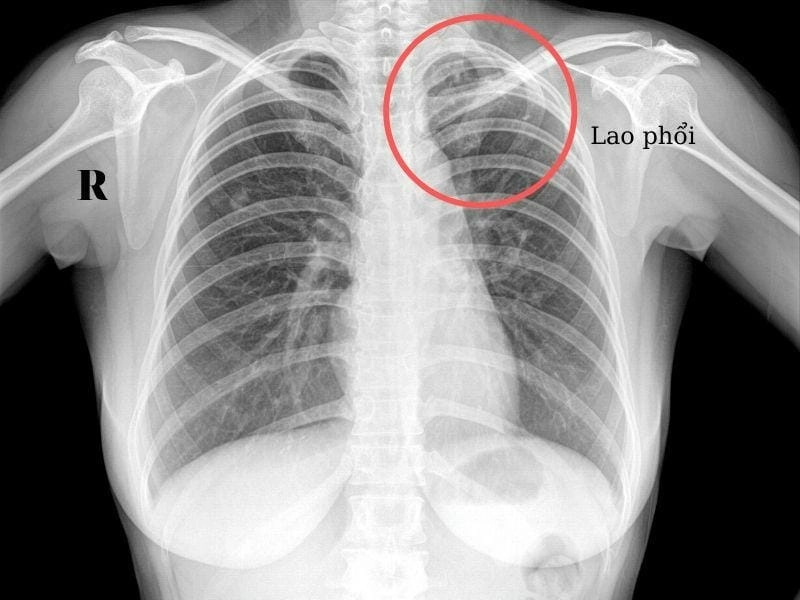

Bạn sẽ phải rùng mình khi chiêm ngưỡng hình ảnh bệnh lao phổi là như thế nào dưới ống kính y học thực tế. Những bức ảnh chụp X-quang cho thấy phổi bị tổn thương nặng, xuất hiện những đốm trắng mờ như bóng ma ám ảnh. Không chỉ là các tổn thương vật lý, đây còn là những “chứng tích sống” của căn bệnh âm thầm hủy hoại cơ thể qua từng hơi thở. Từ viêm nhẹ đến tổn thương lan rộng, hình ảnh bệnh lao phổi khiến người xem không thể rời mắt vì mức độ nghiêm trọng mà nó thể hiện rõ ràng qua từng chi tiết.

Cảnh báo: tổng hợp ảnh bệnh lao phổi chân thực này không dành cho người yếu tim. Đây là loạt hình ảnh y khoa được các chuyên gia sưu tầm và xác thực, ghi lại quá trình tiến triển của bệnh từ giai đoạn đầu đến giai đoạn nguy kịch. Từng mảng mô phổi bị ăn mòn, xơ hóa, hoại tử được phơi bày rõ nét dưới ánh sáng X-quang lạnh lùng. Những hình ảnh này không chỉ mang tính chất minh họa y học, mà còn là hồi chuông cảnh tỉnh cho bất kỳ ai còn lơ là với căn bệnh nguy hiểm này.

Chuẩn đoán chính xác nhờ hình ảnh x quang lao phổi